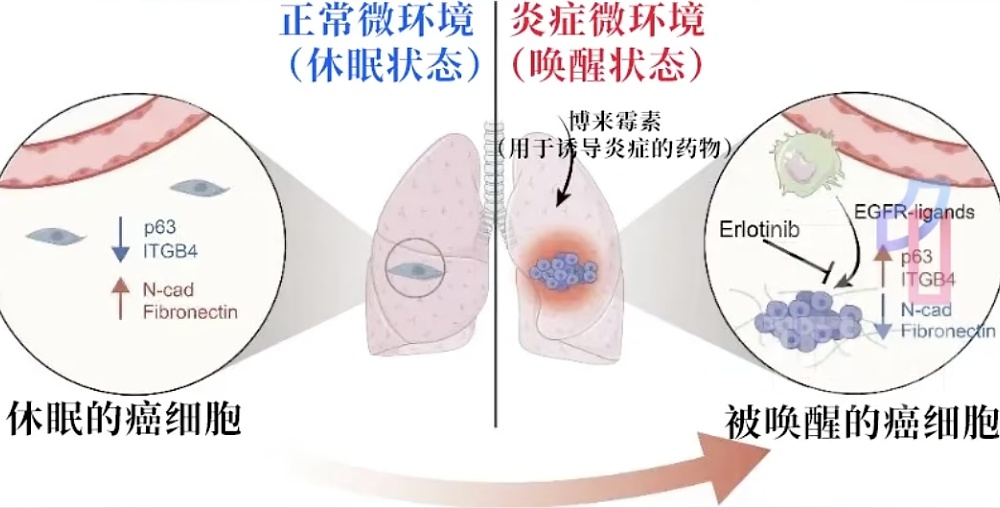

2025年9月,中国科学院、麻省理工学院的研究人员在《美国国家科学院院刊》上刊发的一项研究发现:炎症可以唤醒远端转移的休眠癌细胞,从而引发癌症转移和复发。

也就是说,处于睡眠状态、不构成威胁的癌细胞,在遇到炎症的刺激后,就像被一把钥匙打开,会立刻苏醒,重新获得分裂和形成肿瘤的能力。